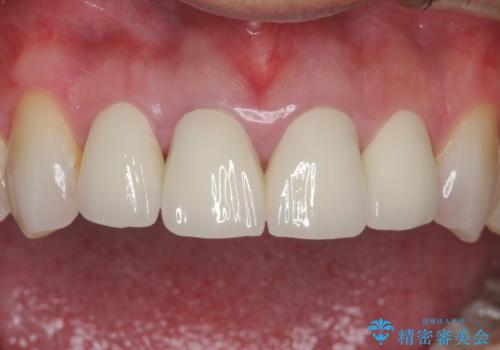

昔装着したかぶせ物を自然な色にしたい オールセラミックによる審美的改善

- 前歯のかぶせ物を自然な色味のものにしたいとのことで、来院されました。

保険適用のかぶせ物が装着されており、適合も悪く、変色している状態でした。

土台からの、再治療を行い、オールセラミッククラウンの装着を行う計画としました。

審美的な改善はもちろんのこと、ぴったりとしたものを装着することで、歯茎の発赤も改善されました。